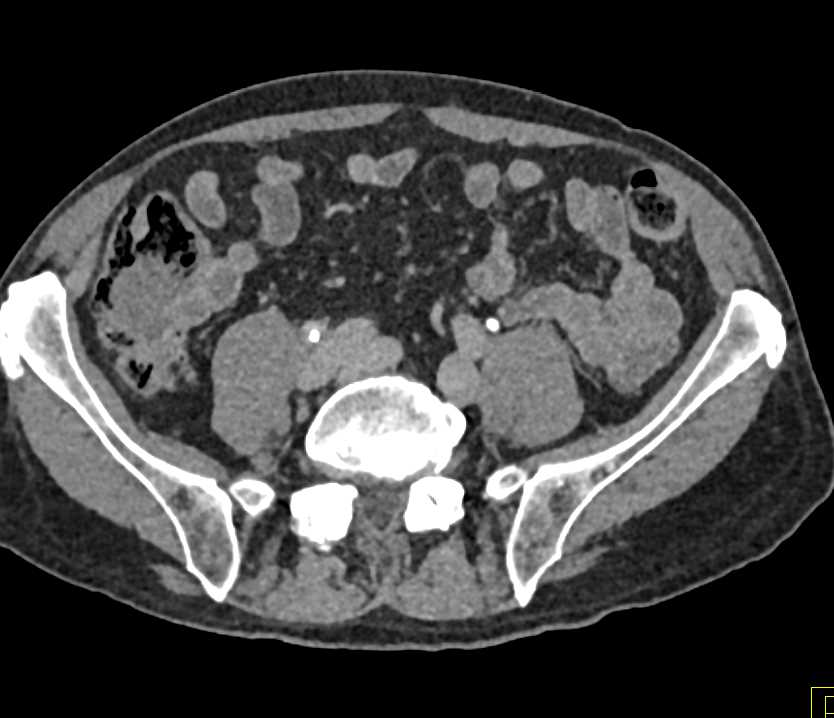

Medullary Sponge Kidney